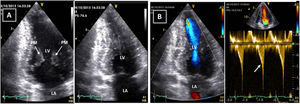

Transthoracic echocardiogram after detraining. Note the abnormal shape of the left ventricular cavity (small cavity size, prominent papillary muscle, with apical cavity obliteration in systole (A) and increased flow velocity (arrow) (B) suggestive of a myopathic left ventricle, rather than adaptive remodeling following training. LA: left atrium; LV: left ventricle; RA: right atrium; RV: right ventricle.